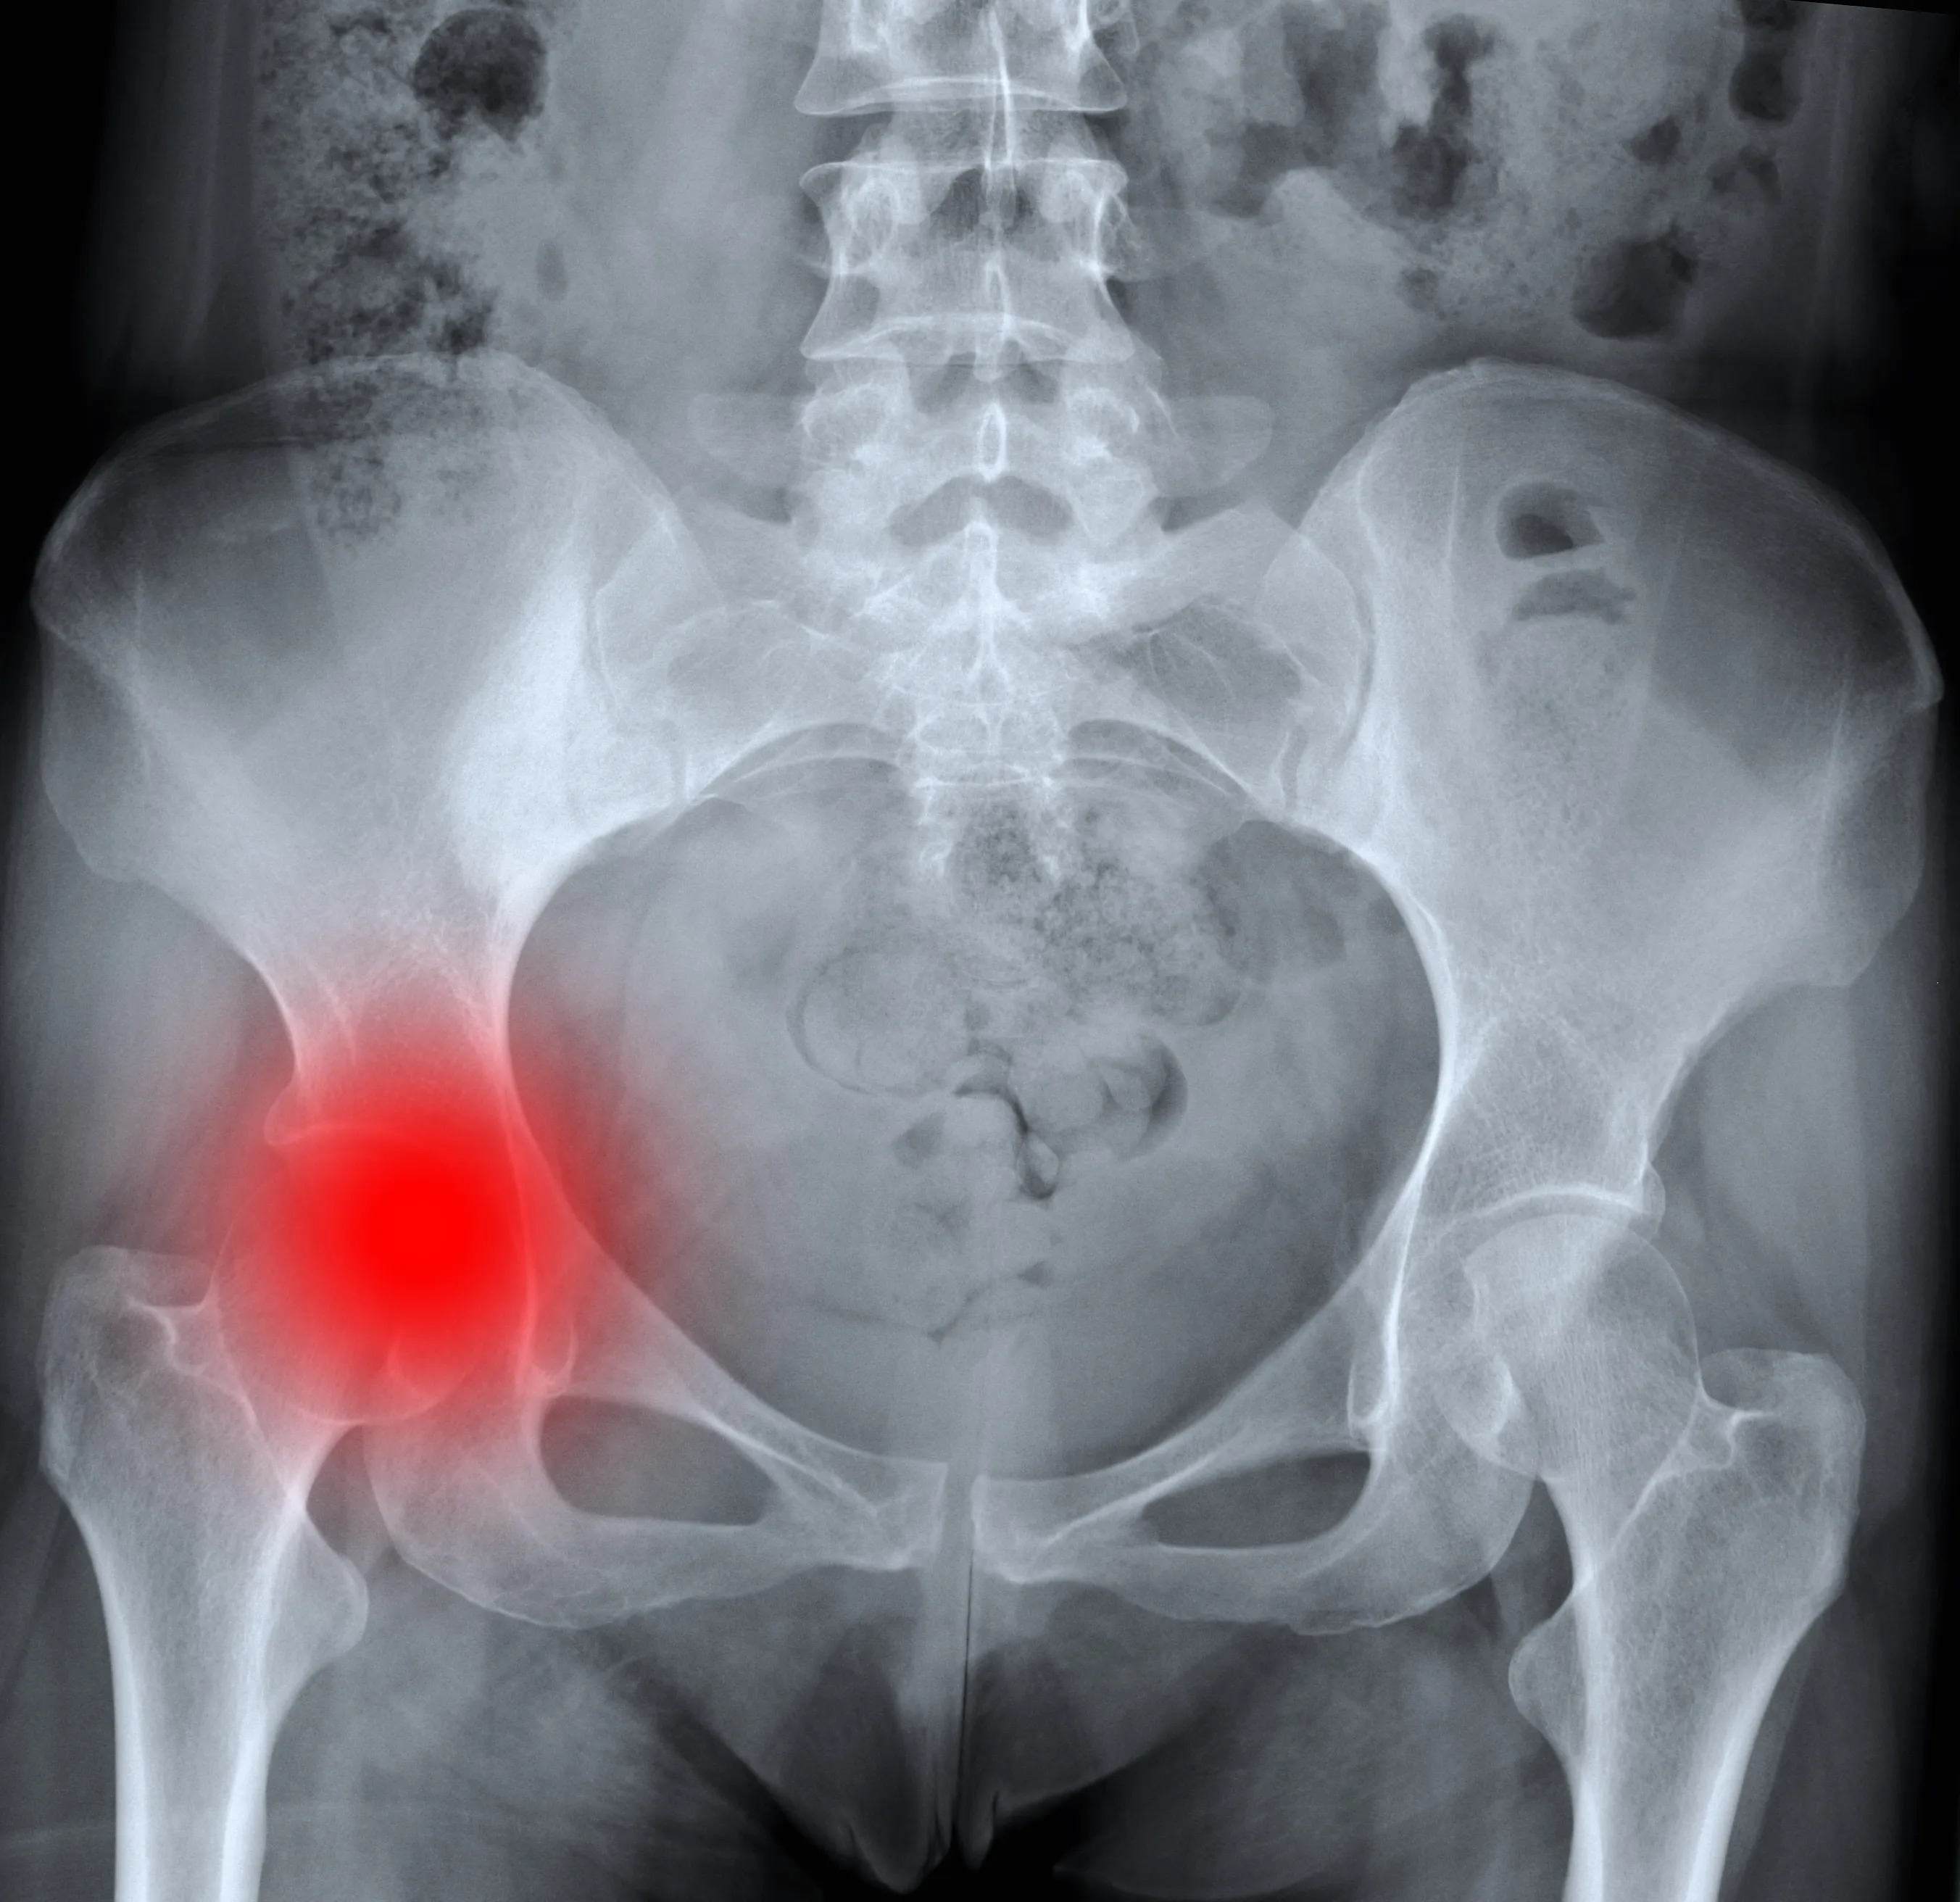

한국인에게 흔한 고관절 질환은 '고관절 충돌 증후군', '고관절 골관절염', '대퇴골두 무혈성 괴사' 등의 질환입니다. 이외에도 질환은 아니지만 노년기에 골밀도가 감소하면서 낙상으로 인한 '고관절 골절'도 흔한 문제로 나타날 수 있습니다.

고관절 질환 1. 고관절 충돌 증후군

고관절을 이루는 비구(골반의 컵 모양 소켓)와 대퇴골두(허벅지 뼈의 공 모양 끝부분), 그리고 경부(대퇴골두와 허벅지 뼈를 연결하는 부위)의 구조가 서로 충돌하면서 통증을 일으키는 질환입니다. 관절 사이의 충돌이 오랜 기간 반복되면 충돌 부위의 관절 연골이 손상되고, 비구(소켓에 붙어 있는 연골)나 대퇴골에 붙어 있는 섬유 연골 조직이 찢어져 통증을 유발할 수 있습니다.